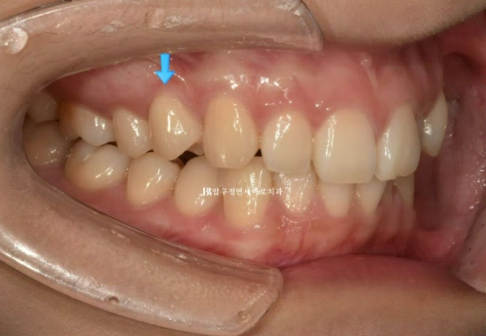

23.10

파란 화살표는 왜소치입니다.

우측 사진에서 첫번째 작은어금니 교합이 떠 있는 것이 보입니다.

통상 앞니 부분교정은 송곳니에서 송곳니까지 6개 앞니만을 대상으로 하지만, 작은 어금니 교합도 개선하기 위해서

송곳니 뒤쪽 1개씩 총 8개 치아에 장치를 붙이기로 했습니다.